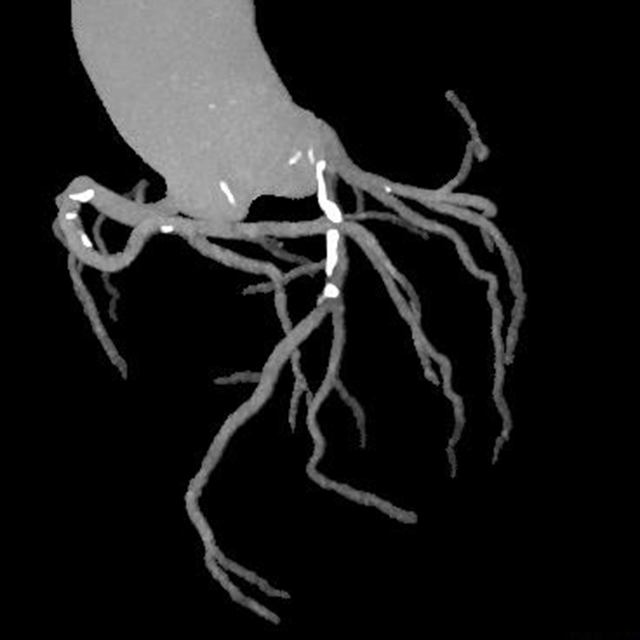

术后检查

2.主动脉夹层的检测:这一检查能够清楚地显示主动脉的解剖结构,帮助医生观察主动脉夹层并确定其位置和严重程度,及时进行干预。